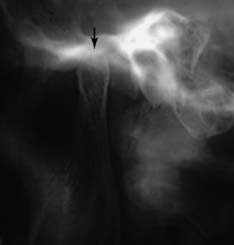

Special radiographs may be needed for the assessment of TMJ disorders and a wide variety of pathologies ranging from bone and mineral disorders to metabolic disorders, genetic abnormalities, and soft tissue calcifications such as carotid artery calcification.21 For assessment of the TMJs, a transcranial exposure (Fig. 1-25), with the help of a positioning device, reveals the lateral third of the mandibular condyle and can be used to detect structural and positional changes. However, interpretation may be difficult,22 and more information may be obtained from other images23 (Fig. 1-26).